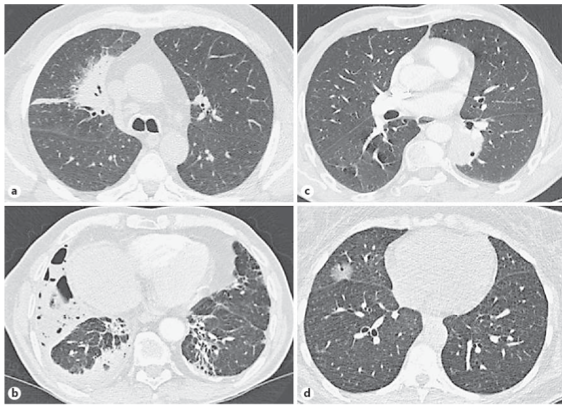

診断には、CT検査やPET検査が重要な役割を果たします。これらの検査によって、腫瘍の大きさや位置、

周囲の組織への影響を評価することができます。

各リンパ節にも異常がないということで、まずは一安心です。CT検査は、悪性リンパ腫の診断に

おいて非常に重要な検査です。特に、リンパ節の腫れや異常な影が見られる場合、

さらなる精密検査が必要となります。